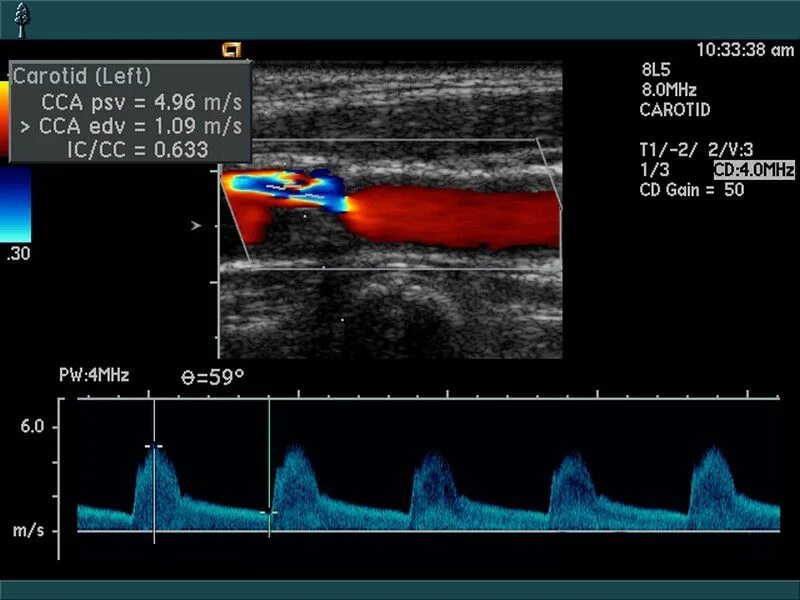

Атеросклероз на узи